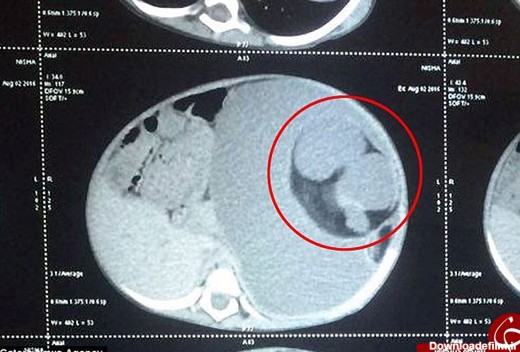

در کشور هندوستان یک دختر بچه 15 ماهه به نام نیشا به وسیله پزشکان تحت عمل جراحی قرار گرفته و از معده او دو جنین تکامل نیافته به اندازه دو توپ تنیس خارج شده است.